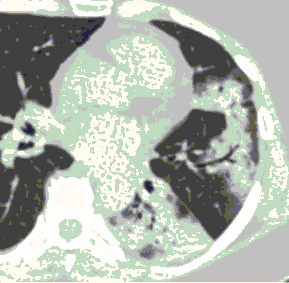

КТ имеет высокую чувствительность в выявлении изменений в легких, характерных для COVID-19. Применение КТ целесообразно для первичной оценки состояния ОГК у пациентов с тяжелыми прогрессирующими формами заболевания, а также для дифференциальной диагностики выявленных изменений и оценки динамики процесса. КТ позволяет выявить характерные изменения в легких у пациентов с COVID-19 еще до появления положительных лабораторных тестов на инфекцию с помощью МАНК. В то же время, КТ выявляет изменения легких у значительного числа пациентов с бессимптомной и легкой формами заболевания, которым не требуется госпитализация. Результаты КТ в этих случаях не влияют на тактику лечения и прогноз заболевания при наличии лабораторного подтверждения COVID-19. Поэтому массовое применение КТ для скрининга асимптомных и легких форм болезни не рекомендуется. При первичном обращении пациента с подозрением на COVID-19 рекомендуется назначать КТ только при наличии клинических и инструментальных признаков дыхательной недостаточности (SpO2 < 95%, ЧДД > 22).

4. Все выявляемые при лучевых исследованиях признаки, включая КТ-симптомы, не являются специфичными для какого-либо вида инфекции и не позволяют установить этиологический диагноз. Вне клинической (эпидемической) ситуации они не позволяют отнести выявленные изменения к пневмонии COVID-19 и дифференцировать их с другими пневмониями и невоспалительными заболеваниями. Данные лучевого исследования не заменяют результаты обследования на РНК SARS-CoV-2. Отсутствие изменений при КТ не исключает наличие COVID-19 и возможность развития пневмонии после проведения исследования.

15. Рекомендации по формированию описаний и оценке изменений в легких и ОГК при имеющейся/подозреваемой пневмонии COVID-19 представлены в Приложении 1.